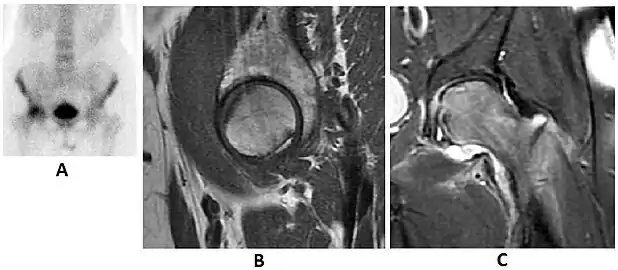

Figure 8:

X-ray of a patient with transient osteoporosis of the left hip showing osteoporosis.[1]

Coronal stir imaging in transient osteoporosis, showing diffuse edema.[1]

Scintigraphy (A), sagittal T1 (B), and coronal PD fat sat of a patient with a subchondral fracture of the femoral head with convex shape to the articular surface.[1]

Coronal T1 of a patient with avascular necrosis of the femoral head.[1]